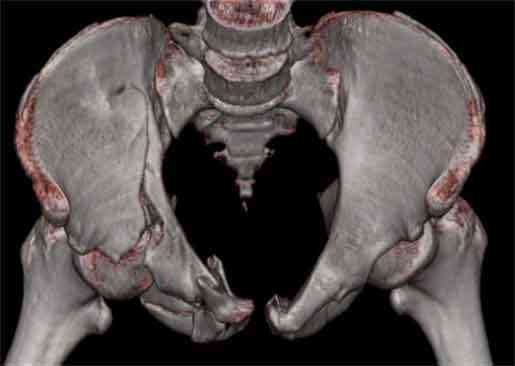

Не смог разглядеть на представленных картинках частичное повреждение левого КП, повреждение Денис1-2 справа? 3Д реконструкции в инлет и боковой проекциях убедительно не демонстрируют типа повреждения задних отделов тазового кольца(справа боковая масса скомпремирована), Наверное, у тебя есть возможность оценить тип перелома крестца по прямой проекции 3Д.

По поводу классификации повреждения тазового кольца( по тем данным . что видны на представленных картинках):

по Pennal et al.- латеральное компрессионное повреждение тип В(ротационно-нестабильное (внутренняя ротация), вертикально стабильное)

по Tile classif. тип В2-1 - частично стабильное повреждение с неполным разрывом задней дуги.

По вертлуге- смог разглядеть только изолированный перелом передней колонны.

Насколько я понял из твоего письма, обращенного к анонимному vit, ты не видишь показаний к реконструкции перелома. Я бы взялся за реконструкцию(илео-ингвинальный доступ), хоть прошел и месяц после травмы: боковая 3Д показывает смещение нагрузочной зоны впадины, что однозначно будет способствовать разрушению хряща головки и впадины( особенно у 16 летнего пациента с ожидаемым высоким уровнем активности) + изменение геометрии впадины за счет неустраненного смещения фрагментов колонны (КТ, 3Д данные).

На мой взгляд, без реконструкции этот сустав обречен (концепция вторичной конгруэтности в данных условиях работать не будет), реконструкция дает шанс на восстановление функции сустава.

В данном случае 3D и корональные срезы КТ менее информативны, чем поперечные. Согласен с левосторенним минимальным повреждением КПС, но не смог уловить перелом крестца.

На 3D по линии перелома ацетабулум возможно сверху в подздошной кости уже есть сращение? или состояние перелома у молодых, после неполного (при пластической деформации) перелома.

По представленным материалам, мне кажется, перелом был передней колонны ацетабулум с минимальным вовлечением нагрузочной поверхности сустава, левосторенний повреждение КПС и лонных костей.